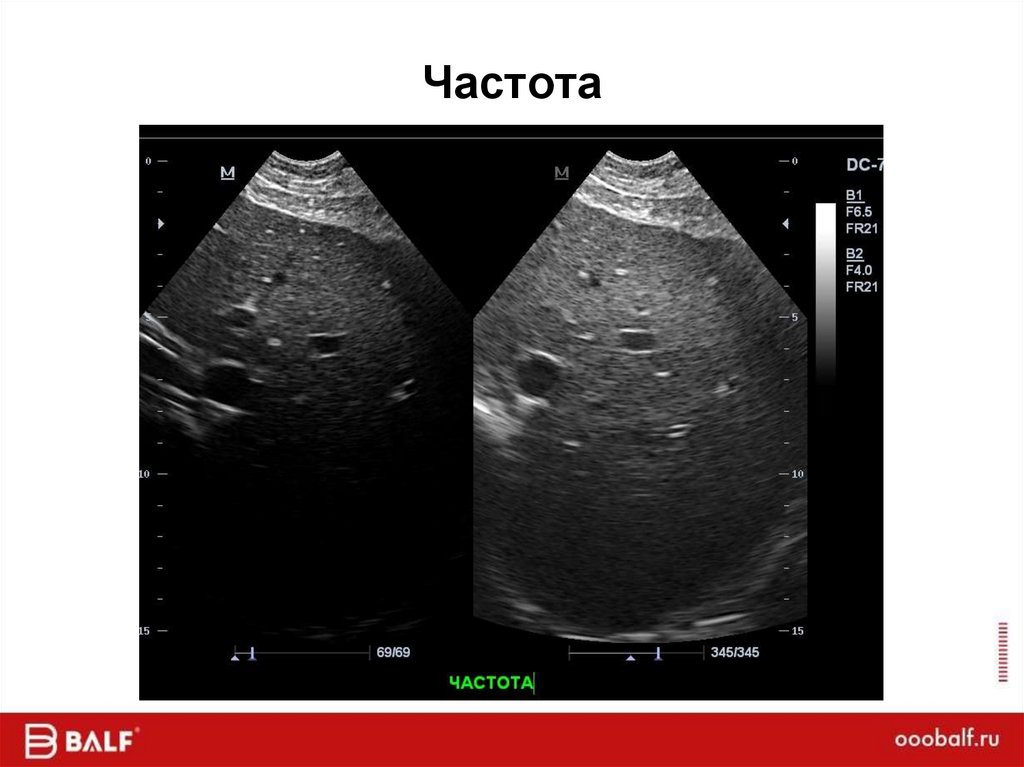

Частота

Портативный

49. Частота